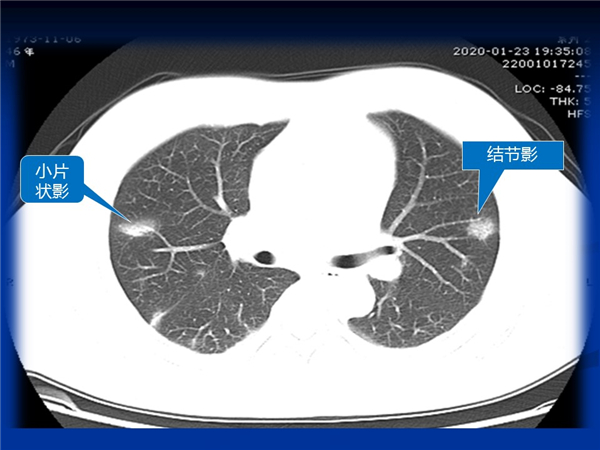

【病例分享】新型冠狀病毒感染肺部CT影像4例(常德市第一人民醫(yī)院)